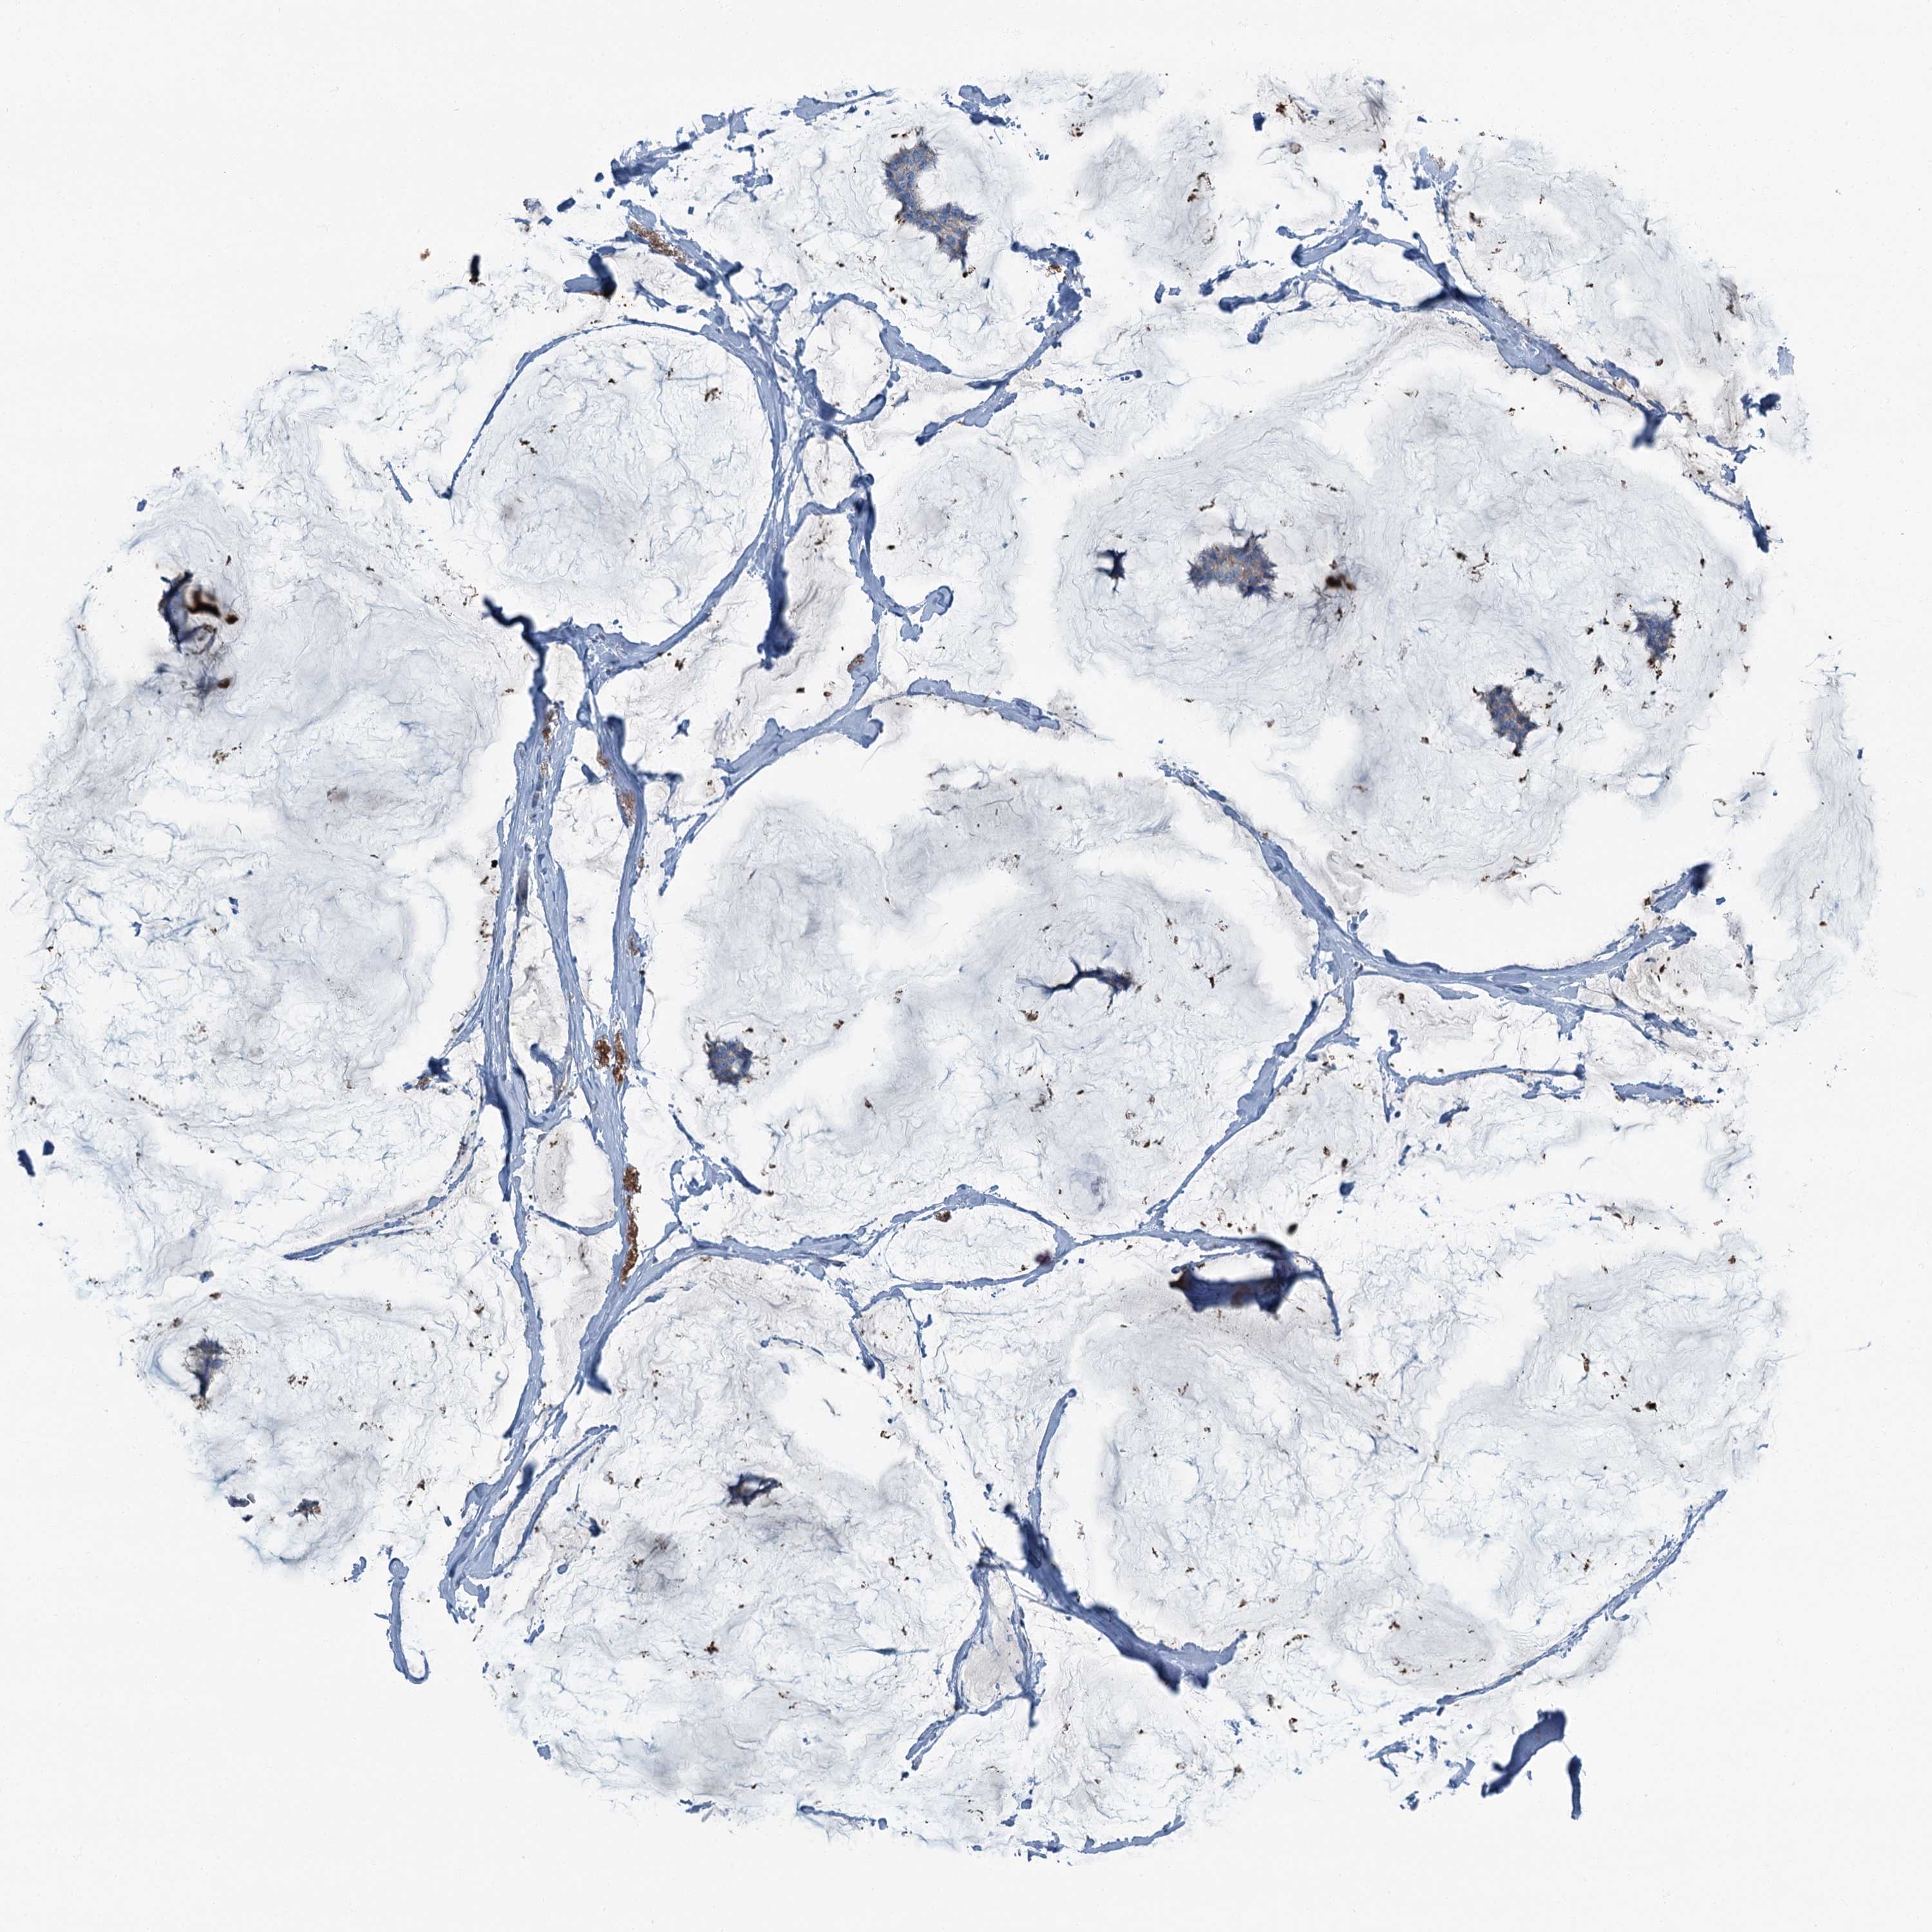

BRCA TCGA BRCA VALIDATION PROTEIN EXPRESSION